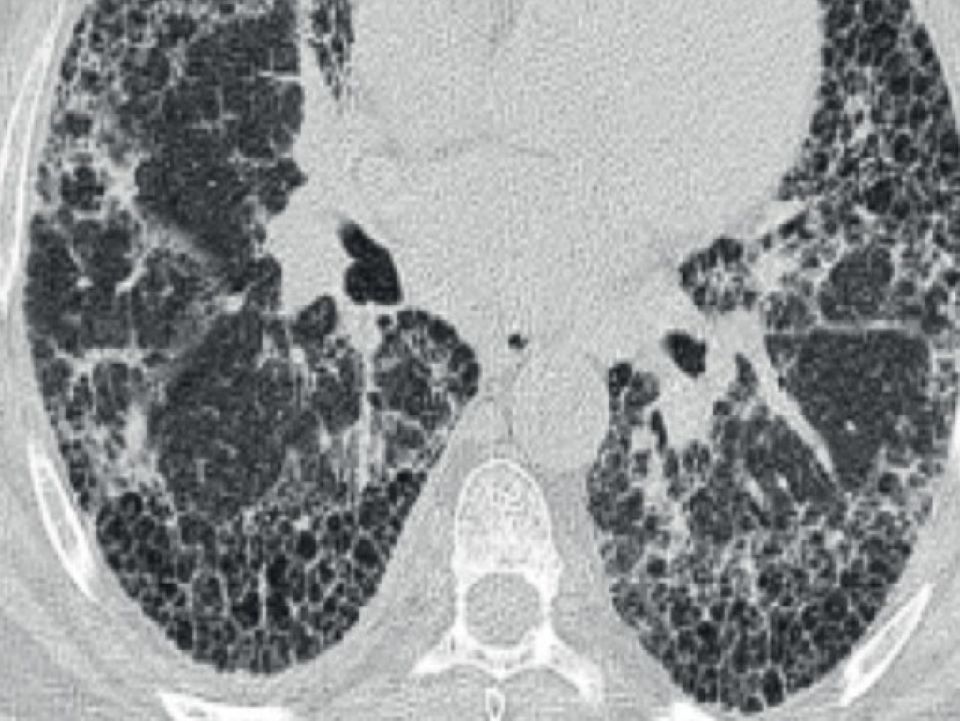

Du 23 avril au 24 avril 2026 le Dr Julien Cohen du Service de radiologie des HUG et le Pr Gilbert Ferretti du Service de radiologie, CHUGA Grenoble/FR vous invitent à participer un atelier d’imagerie afin de découvrir les subtilités du scanner thoracique dans le diagnostic et le suivi des pneumopathies interstitielles diffuses.

• 9h30 | Patterns UIP / PIC

• 11h | Patterns NSIP

• 14h20 | Pneumonies d’hypersensibilité